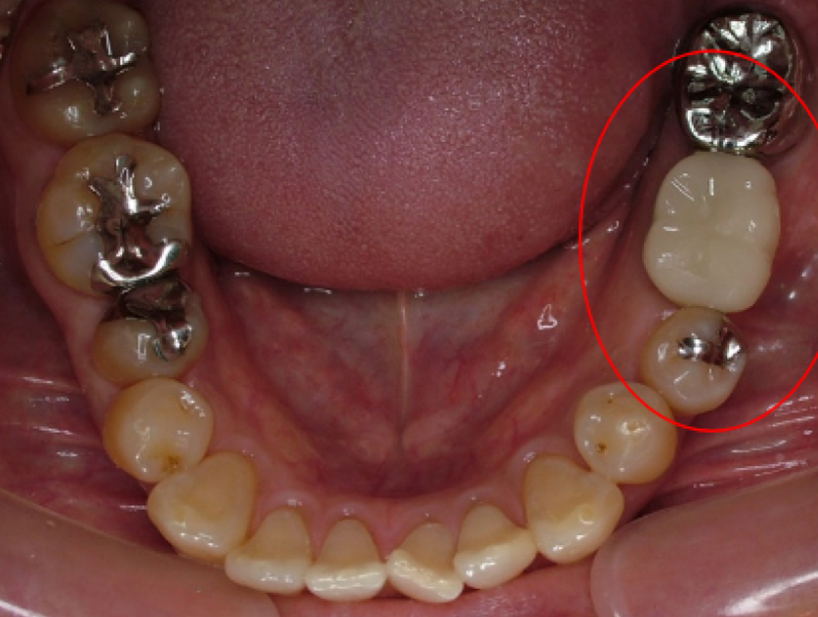

治療前治療後

| 治療内容 | インプラント奥歯1本・根管治療・矯正治療(圧下) |

|---|---|

| 患者様の年齢 | 40歳 |

| 患者様の性別 | 男性 |

| 治療期間 | 1年 |

| 治療回数 | 矯正治療合わせて50回程度 |

| 治療費用 | 根管治療1歯6万円/インプラント治療1歯50万円 矯正治療:1歯 10万円 |

| 治療で得られるメリット |

|

| 治療する際に起こる リスク・副作用 |